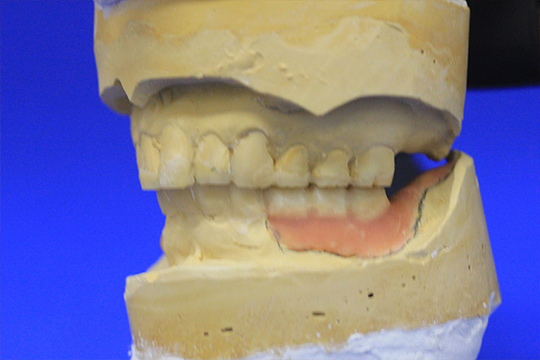

ディグマのデータを元に模型上で理想的な口腔内を再現します。